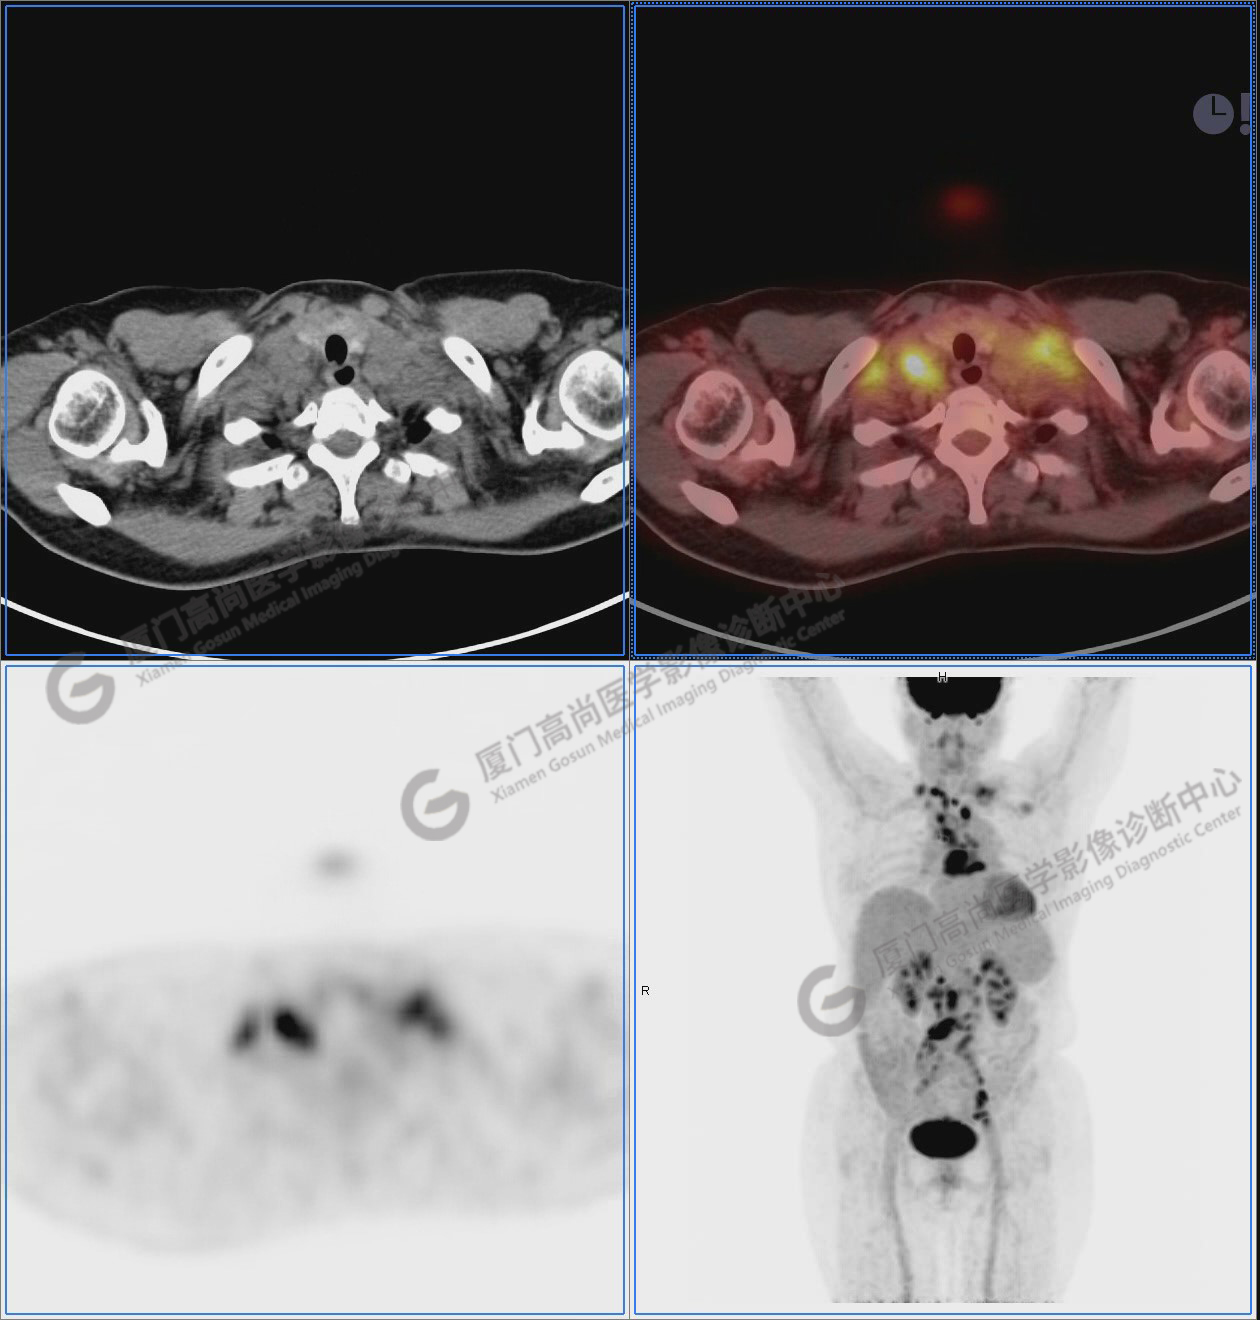

圖2-9:雙側(cè)鎖骨區(qū)、縱隔、右側(cè)內(nèi)乳區(qū)、腸系膜緣、腹膜后、雙側(cè)髂血管旁及盆腔多發(fā)腫大淋巴結(jié)影,代謝不同程度增高,考慮為轉(zhuǎn)移。

圖2

圖3